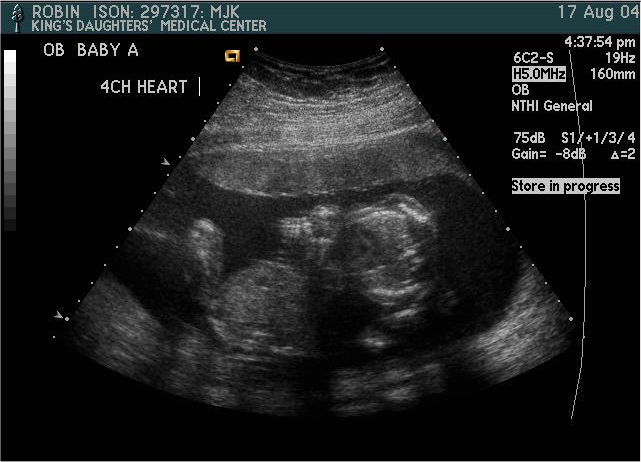

Baby A

Pictures from Ultrasound at 20 weeks.